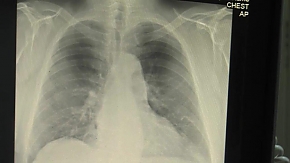

A százhalombattai önkormányzat évtizedek óta szervez tüdőszűrést a lakcímkártyával rendelkezők részére a lakosság egészségmegőrzése érdekében. A tüdőszűrés alkalmas a TBC, illetve sok más tüdőbetegség időben történő felismerésére. A TBC és a tüdőrák kezdeti stádiumában tünetmentes, ezért különösen fontos, hogy akkor is rendszeresen vegyünk részt szűrővizsgálatokon, ha semmiféle panaszunk nincs – olvasható Vezér Mihály polgármester közleményében.